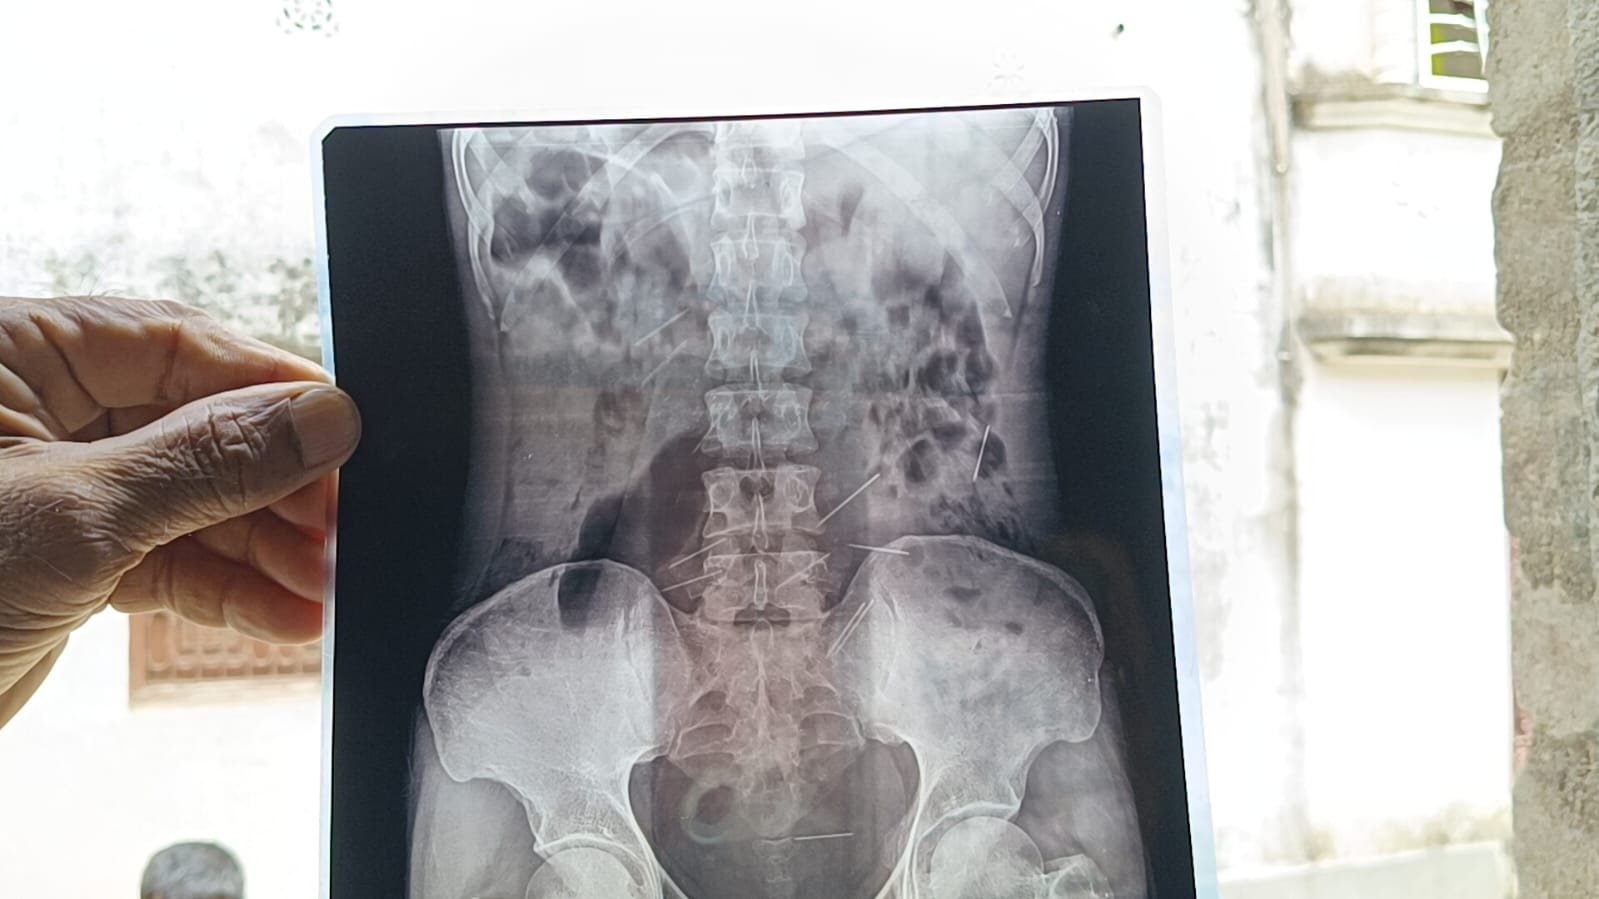

হায়দারের এক আত্মীয় মহম্মদ সাকির শেখ বলেন, “গত দেড় বছর আগে হায়দার যখন শরীরের যন্ত্রণায় ছটফট করছিল। তখন ওকে মালদা মেডিকেল কলেজে চিকিৎসার জন্য নিয়ে যাওয়া হয়। এক্স-রে রিপোর্ট দেখার পরেই সকলের চক্ষু চড়কগাছ হয়ে যায়। হায়দারের হাতে, পেটে, পিঠে কিলবিল করছে সূচ। গত দুই মাস আগে সামসেরগঞ্জের একটি নার্সিংহোমে অস্ত্রোপ্রচার করে হায়দারের শরীর থেকে দুই দফায় মোট প্রায় ৩০টি সুচ বার করেছিলেন চিকিৎসকেরা। সেই সুচ বেশ বড় সাইজের। আবারও নাকি হায়দারের শরীরে অসংখ্য সূচ দেখা দিয়েছে।”

এদিকে হায়দারের শরীরের এই সুচ কাণ্ড নিয়ে রীতিমতো আতঙ্কিত পাড়া-প্রতিবেশীরা। স্থানীয় বাসিন্দা মহম্মদ আনারুল শেখ ও যশোদা বর্মনদের বক্তব্য, “এমন অসুখের কথা জীবনে কোনদিনও শুনিনি। জীবন্ত মানুষের শরীরে অসংখ্য সুচ। এটা ভাবাই যায় না। এক্স-রে ছবিতে হায়দারের দুই হাতে, পেটে অসংখ্য সুচ ধরা পড়েছে। এটা কি করে সম্ভব। এই ঘটনার পিছনে অবশ্যই কিছু অন্য কারণ রয়েছে।” তবে এই ঘটনার পেছনে ‘কালা জাদু’র কোনও ঘটনা জড়িত নেই বলে দাবি করেছে পশ্চিমবঙ্গ বিজ্ঞান মঞ্চের জেলা সম্পাদক মনোরঞ্জন দাস। মালদার মুখ্য স্বাস্থ্য আধিকারিক ডাঃ সুদীপ্ত ভাদুড়ি বলেন, “আগে দেখতে হবে ওই যুবক কোনও সময় মাদকাসক্ত ছিল কিনা। অনেক ক্ষেত্রে দেখা যায় ইনজেকশনের সিরিঞ্জ ব্যবহার করে নেশা করে থাকে কেউ কেউ। শরীরে সুচ ঢুকে থাকলে সেটার একটা প্রতিক্রিয়া রয়েছে। তবে এই ধরনের ঘটনার ক্ষেত্রে আগে রোগীকে আমরা মানসিক দিক দিয়ে পর্যবেক্ষণ করে দেখব। জেলা স্বাস্থ্য দপ্তরের একটি টিম ওই যুবকের বাড়িতে যাবে।” চিকিৎসকরা বলছেন, মানবদেহে কখনো সুচের জন্ম হয় না। তাঁদের যুক্তি, যেহেতু ওই যুবক মানসিক রোগী তাই হয়ত নিজে নিজেই সে শরীরের মধ্যে সুচ ঢুকিয়েছে, না হলে যেহেতু ওই যুবক মূক ও বধির তাই তাকে সুস্থ করে তোলার নাম করে কোনও ওঝা তার দেহে সুচ ঢুকিয়ে দিয়েছে। তবে সমস্তটাই এখন খতিয়ে দেখা হচ্ছে।